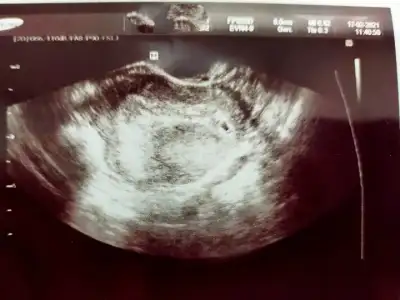

O kadarlıkken benim de görünmemişti normalBenimde dün gördük canım keseyi sat a göre dün 4+5 di...yolk saç vs görünmedi ..Ama erken dimi ?

Kız bende attım kese fotosunu görebilirsensayet yorumlarmisin?4+5 adetine göre dedin herhalde. Crl ölçmemiş çünkü. Bide küçük ölçmüş o çentikler hiç uçtan uca değil. Dr'unu değiştir bence. Bu sefer küçük ölçer, bidahakine büyük ölçer boş yere kafa karışıklığıBenim ilk gittiğim de büyük ölçmüştü. Yani öyle ölçmek için kör olmak lazımdı

Bakiyim canımKız bende attım kese fotosunu görebilirsensayet yorumlarmisin?

Kese 4 mm yakın ölçmüş ama ben ölçüm çentiğini göremedim canım. Kesenin etrafı iyi kalınlaşmış aslında. Günü için de 5+1 demiş ama kese 4 mm iken 5+1 olamaz. Onu nasıl hesaplamış cihaz anlamadımBilmiyorum ki canım kaç olmadı gerektiğini Dr bı kızardı bozardi zaten bende birşey soramadım yarın tekrar gel dedi

Yok ya ben gördüm. sağda yukarda. Yani etrafı iyi kalınlaşmış demek iyi tutunmuş. 4 mm kese tam kaçıncı güne tekabul eder bilmiyorum canım ama 5+1'den ufaktır.Kese 4mm iken kaç haftalık olur 4mu evet çentikli değil ne biliyom nasıl ölçtü kesenin etrafının iyi kalınlaşması nedir ben zaten hiç birşey anlamadım keseyi gorecem diye zaten aleti içimde bı ora bı bura gezdirdi canımda yandı saklanmış dedi anlamadim dış gebelik olabilirmi?